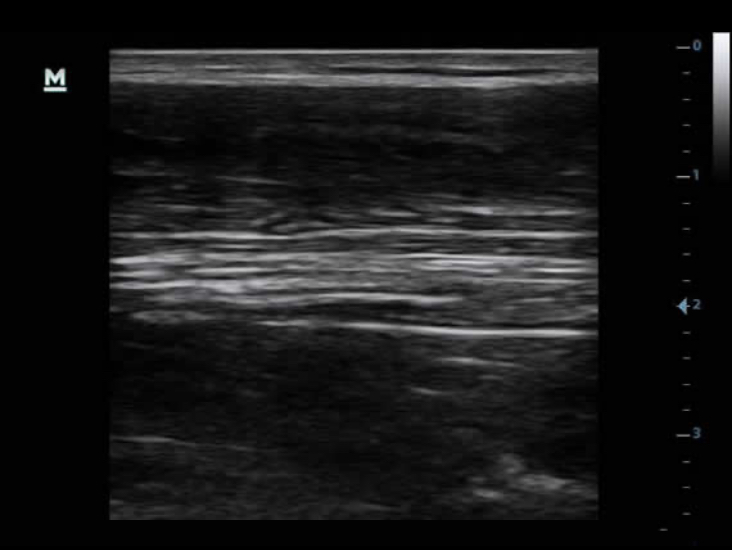

TSI

Las imĂĄgenes tisulares especĂficas optimizan la calidad de la imagen en funciĂłn de las propiedades del tejido que se explora. Hay cuatro opciones de imĂĄgenes disponibles: general, muscular, de fluidos y de grasa.